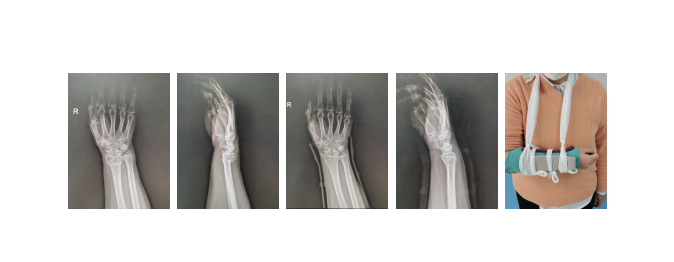

患者马女士,65岁,因在凤凰工业园家中干活时滑倒摔伤,右腕部着地,前往我院骨创伤科就诊,拍片发现桡骨远端骨折、断端嵌插、且复位后无法维持有效固定。通常来说,切开复位内固定是常见的治疗方式,但同时也有一定的缺点,如创伤大、出血多,容易造成血管、神经、肌肉损伤,导致关节黏连、肢体活动障碍、骨折不愈合等并发症的发生。我院骨创伤科针对患者病情,给予麻醉下手法整复、闭合穿针、3D打印小夹板固定,使骨折端解剖复位并能持续维持稳定,预后良好。我院骨科还将较为前沿的3D打印技术灵活应用到临床,对于骨折线波及桡骨远端关节面、手法复位不佳或者骨折端不稳定的患者,3D打印技术会针对患者的肢体形态打印出适合个体差异的桡骨远端带孔小夹板,闭合复位后于孔内进行闭合穿针固定,轻便透气,无需切口缝合,辅以中药内服外用,起到良好效果。多年来,我院骨科采用微创结合中医中药干预,治疗前臂尺桡骨骨折,收到满意的临床疗效。

是指桡骨远端关节面3cm以内的骨折,这个部位是松质骨与密质骨的交界处,属于解剖薄弱处,一旦遭受外力,很容易造成骨折。所以它是最常见的前臂骨折,多由于跌倒引起,出现餐叉样畸形。在我院,通过拔伸、掌屈、尺偏等手法进行复位,采用小夹板固定,一般能达到解剖复位,适用于大部分桡骨远端骨折的情况。